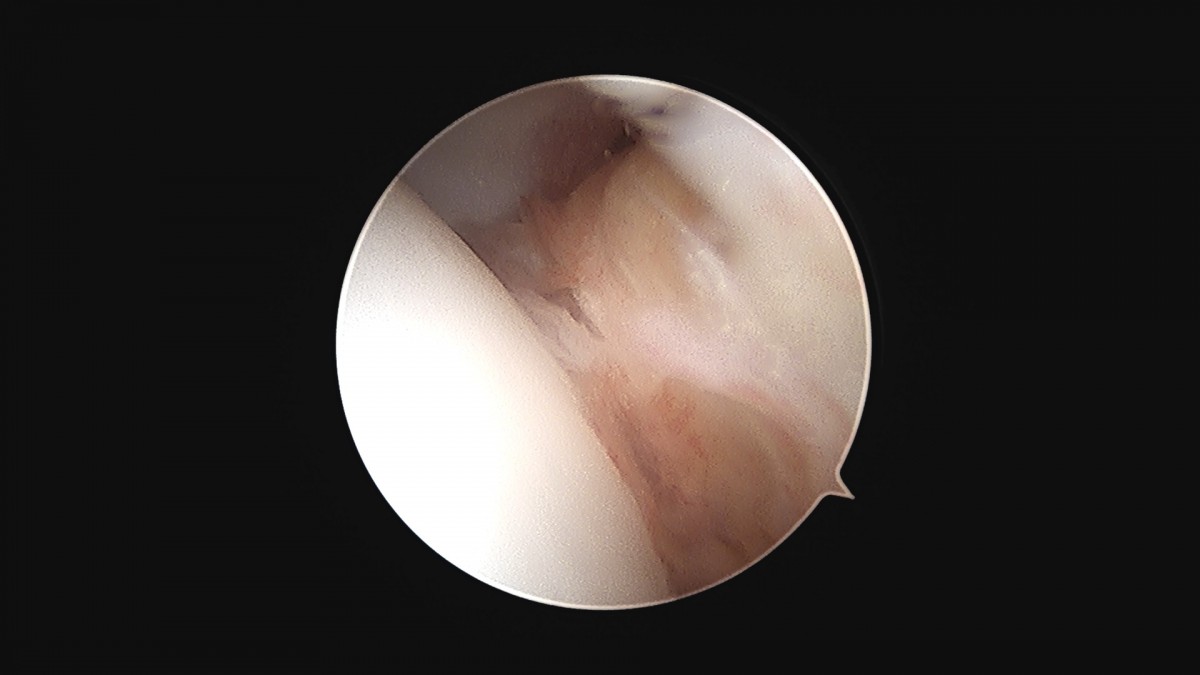

이재상원장님 발목 활액막 절제술 및 인대 봉합술 신진O 환자

dae765e4d9ac96aee867c9d6292d8784_1758003733_017.jpg